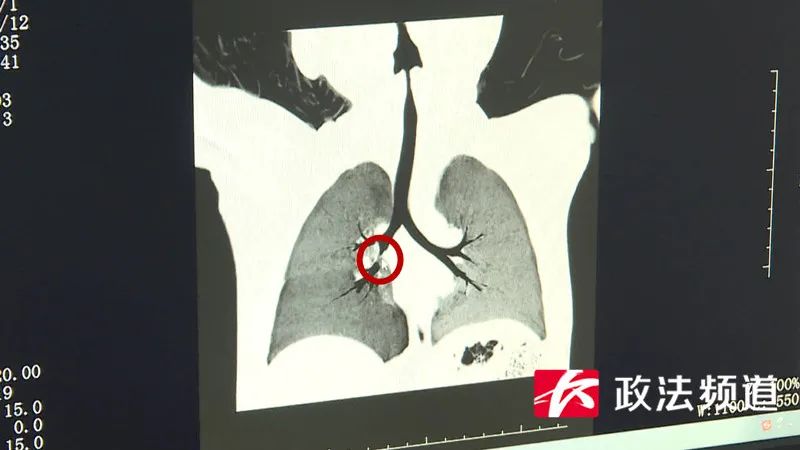

▲圖釘就卡在紅圈處

“從CT上可以看到,異物已經(jīng)卡在右側(cè)主支氣管的地方。”湖南省兒童醫(yī)院 耳鼻咽喉頭頸外科醫(yī)師謝麗華告訴記者,情況緊急,醫(yī)院立即組織多學(xué)科醫(yī)護團隊展開救治。在耳鼻咽喉頭頸外科、麻醉手術(shù)科醫(yī)護的默契配合下,大家成功為小明進行了緊急異物取出術(shù)。目前,小明已無大礙。